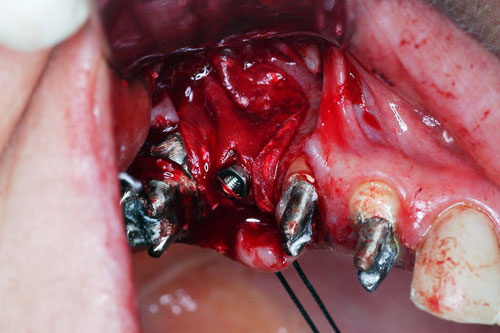

Mientras dichos movimientos ortopédicos se producen (período que supondrá otros seis meses), estudiamos los actos quirúrgicos a realizar en los cuatro implantes que pondremos. De acuerdo al estudio Desatascan realizado observamos tres situaciones diferentes: 1º-El Primer Molar Inferior Izquierdo, lo instalamos mediante Cirugía Minimamente Invasiva , con la aplicación de una Férula Quirúrgica Obtenida de los datos del scanner tratados con un programa de CMI (Cirugía Minimamente Invasiva), previa prueba en un modelo estereolitográfico, ya que la altura ósea era apenas de 9 mm. 2º- El Primer Molar Superior Derecho, se implantará mediante una ligera Elevación Atraumática (Trans alveolar) de Seno una vez logrado el espacio mesio distal necesario. 3º- El Incisivo Central Superior Derecho ausente, cuenta con un sustrato óseo prácticamente inexistente. El espesor de la tabla era de menos de 2 mm. Los caminos posibles a seguir para contar con una Rehabilitación de piezas independientes son dos: Optamos por esta segunda opción por ser menos cruenta y no necesitar de una zona dadora. Técnica esta que pondremos en práctica en dos etapas diferidas: 1º-Incisión horizontal palatinizada, incisiones peri rodetes gingivales e incisiones de descarga. Dilatación que comenzamos con dos incisiones de descarga sobre la cortical vestibular realizadas con disco. y el comienzo de la dilatación propiamente dicha mediante una hoja de bisturí, para luego seguir con un periostótomo . Recién después de alcanzada una cierta separación de la cortical vestibular de la palatina, empezamos con los dilatadores roscados. En este punto podríamos haber utilizado sin riesgos un Implante de 3,8 mm de diámetro, pero a fin de mejorar la estética del pilar emergente decidimos rellenar con material osteoconductor y osteoinductor (BiOss) y cubrir mediante membrana reabsorvible ( Bio Guide). 2º-Implantación seis meses después. Mientras se van cumpliendo los tiempos antes mencionados, y comprobamos reiteradamente la funcionalidad de la oclusión con los provisorios, tomamos impresiones definitivas y construimos primero el maxilar inferior, para definir en primer término la porción inferior de la Guía Anterior., y a nivel posterior Curvas y Microplanos. Para luego realizar los cuadrantes premolar- molar del superior: La espera de la regeneración ósea y sus tiempos pertinentes, más la espera de los tiempos de la implantación, nos obligaron a modificar las etapas del protocolo D.AT.O de manera de mantener la –D- mediante el sector superior de la GA. en provisorios, mientras fuimos resolviendo en forma definitiva los demás sectores. Ya pasados los meses necesarios para recrear un hueso adecuado en el área del Incisivo Superior Derecho, procedemos a resolver la implantación de dicha zona, observando que todo el esfuerzo dedicado al mismo había sido inútil, ya que la formación de hueso se produjo minimamente. Cuatro meses después tomamos impresiones del sector Antero Superior de la Guía Anterior, incluyendo el arrastre de un transfer . Seguimos modelando la encía con un nuevo juego de provisorios. Y se construye entonces el sector superior de la Guía Anterior. Se efectúa un control radiográfico a los 6 meses. Se ha intentado mostrar en esta Rehabilitación, que a pesar de las distintas circunstancias de cada paciente, siempre debemos tener en cuenta la necesidad de ejercer la DESOCLUSIÓN del caso como prioridad número uno, para luego perseguir la ALINEACIÓN TRIDIMENSIONAL de las arcadas y obtener así una OCLUSIÓN equilibrada. D.AT.O. ES EL PROTOCOLO QUE DEBEMOS SEGUIR EN TODA REHABILITACIÓN. BIBLIOGRAFÍA 1)William Mc Horris,B.S.,D.D.S. Oclusión. Con especial énfasis sobre :El rol funcional y parafuncional de los dientes anteriores. 2)Von Spee , Craff(Anatomista alemán, describió la curva de compensación de la articulación de molares y premolares).CURVA DE SPEE 1.89 3)Stuart,D.”Some aspects of the inervation teeth.”Procedings of Royal Society of Medicine.20:1675,19274)Muhleman,H. y Savdir,S”Tooth movility-its causes and significance”Journal of Periodontology ,36:153,Marzo ,Abril,1965. 4)Muhleman,H. Y Savdir,S”Toothmovility its causes and significance” Journal of Periodontology,36:153,marzo,abril,1965. 5-Oclusión y Diagnóstico en Rehabilitación Oral. 6-Anatomia Odontológica. 7-A contribution to the study of the movementes of the mandible. 8-Celenza F.W, Nadeskin J.F.,Oclusión.Situación actual. 9-D´Amico 10-Dawson P.E. 11-Huffman –Regenos. 12-Hobo S.-Takayama H.A. 13-Lucia V.O 14-Mc Horris. 15-Mc Horris. 16-Stuart C. 17-Vartan Veshnilian 18-Alvarez Cantoni H. AUTOR:Ratificación del Protocolo en Rehabilitación Bucal a pesar de las incidencias propias de cada caso clínico. A propósito de un caso.

Cubrimos con membrana reabsorvible.

Elevación de membrana mediante periostótomo

Elevación de membrana mediante periostótomo

Esperamos seis meses antes de implantar.

No obstante pudimos implantar satisfactoriamente mediante un implante de 4.2 mm. de ancho y 14 mm. de largo, con una nueva R.O.G.